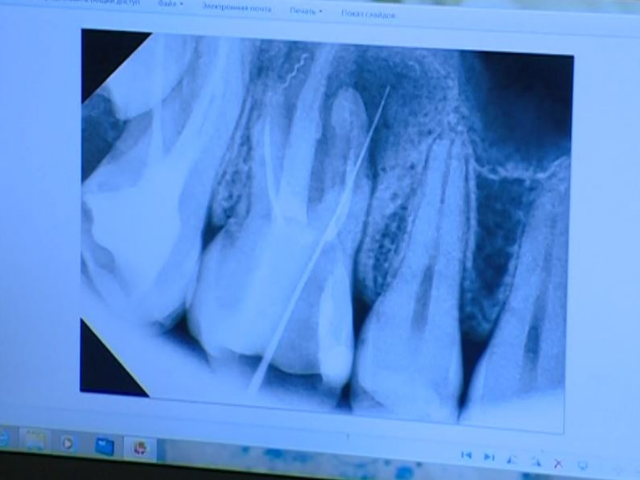

Когда ЛОР отправил девушку делать снимок зубов выяснилось, что под пломбой, в зубных каналах, специалисты обнаружили два давно забытых медицинских инструмента. Они-то и спровоцировали воспаление.

«У меня образовалась киста. Инструменты начали за такой продолжительный период времени окисляться, разрушена кость.Сейчас я уже не могу пролечить зуб, мне нужно будет его только удалять, ставить имплант кости, удалять кисту, вычищать пазуху и ставить уже через полгода имплант зуба», – объяснила пострадавшая Екатерина Горных.